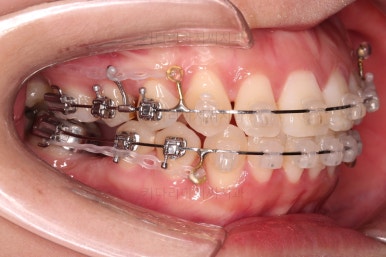

이제 미니스크류가 등장합니다.

상하좌우 발치 공간의 크기와 위치가 제각각이라서 당겨지는 양과 속도가 차이납니다.

그래서 미니스크류를 반드시 써줘야 합니다.

또 다시 얼굴모습 체크.

입매는 서서히 좋아지고 있고요.

약간은 더 들어가도 되지만 너무 많이 들어가면 안되는 상황입니다.

어느새 틈도 다 닫히고요.

마무리 과정만 남았습니다.